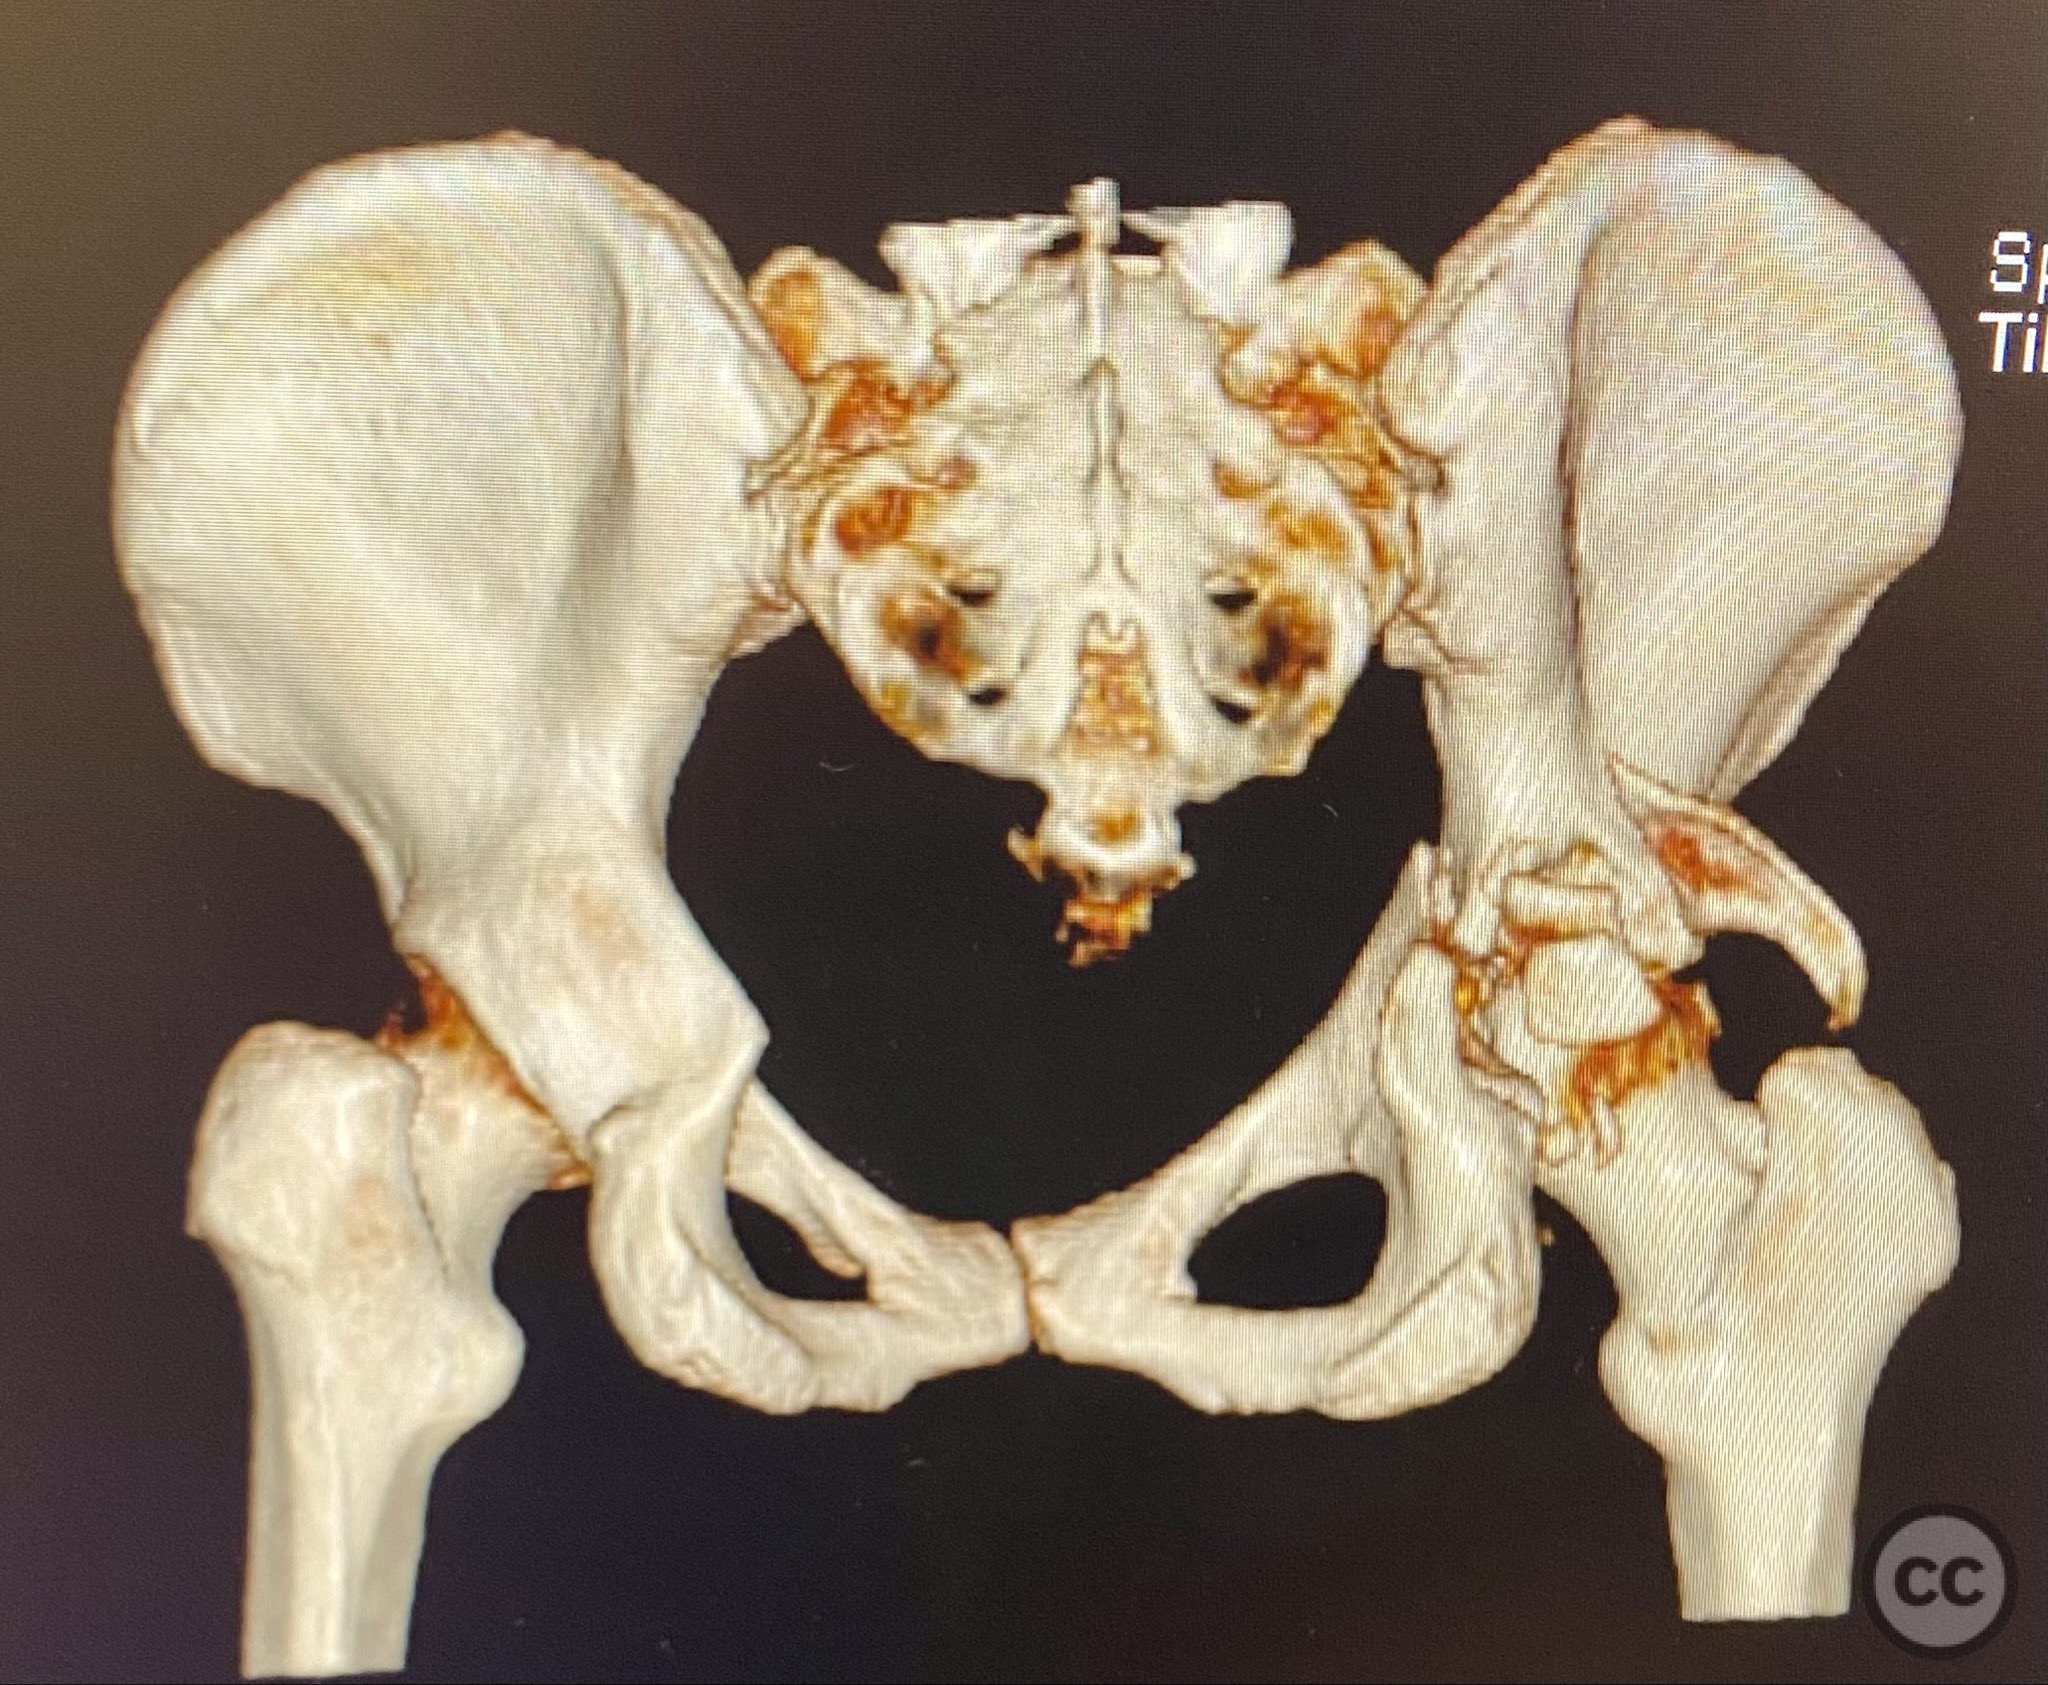

Clinical Details

Clinical and radiological findings:  A high-speed motor vehicle collision resulted in a closed transverse acetabular fracture with associated comminuted posterior wall (PW) fracture-dislocation. The femoral head exhibited impaction and comminution, with local cancellous bone crushed and the femoral head itself also sustaining compressive injury from the denser acetabular bone. Neurovascular examination was unremarkable. Initial CT imaging delineated the acetabular fracture planes, displacement, comminution of the posterior wall, femoral head impaction, and absence of soft tissue attachment to the caudal PW fragment.